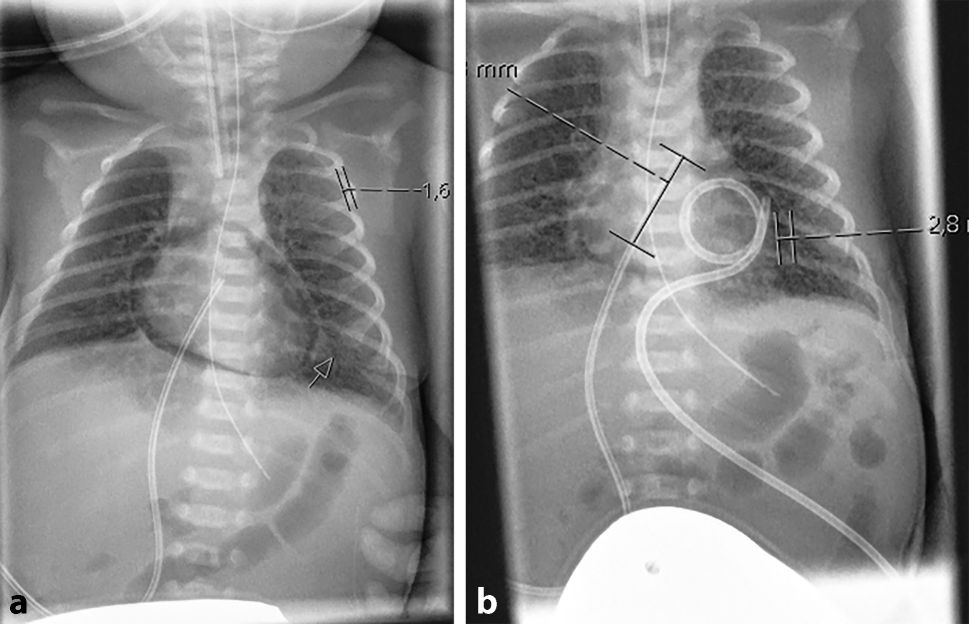

The infant was given two doses of surfactant because of severe respiratory distress syndrome and due to worsening respiratory function, conventional mechanical ventilation was switched to high frequency oscillatory ventilation. On day 2 of life, an echocardiography was performed for PDA (Patent ductus arteriosus) assessment, demonstrating circular air entrapment surrounding the infant’s heart (Video 1). On chest X‑ray, suspected pneumopericardium was confirmed (Fig. 1a), and a pericardial tube was inserted with continuous drainage for 3 days (Fig. 1b). The following day the neonate developed right-sided pneumothorax (Fig. 2a), which mandated the insertion of a chest drain (Fig. 2b).

Fig. 2

a Chest X-ray demonstrating right-sided pneumothorax, b Chest X-ray after insertion of a chest tube (pigtail) catheter